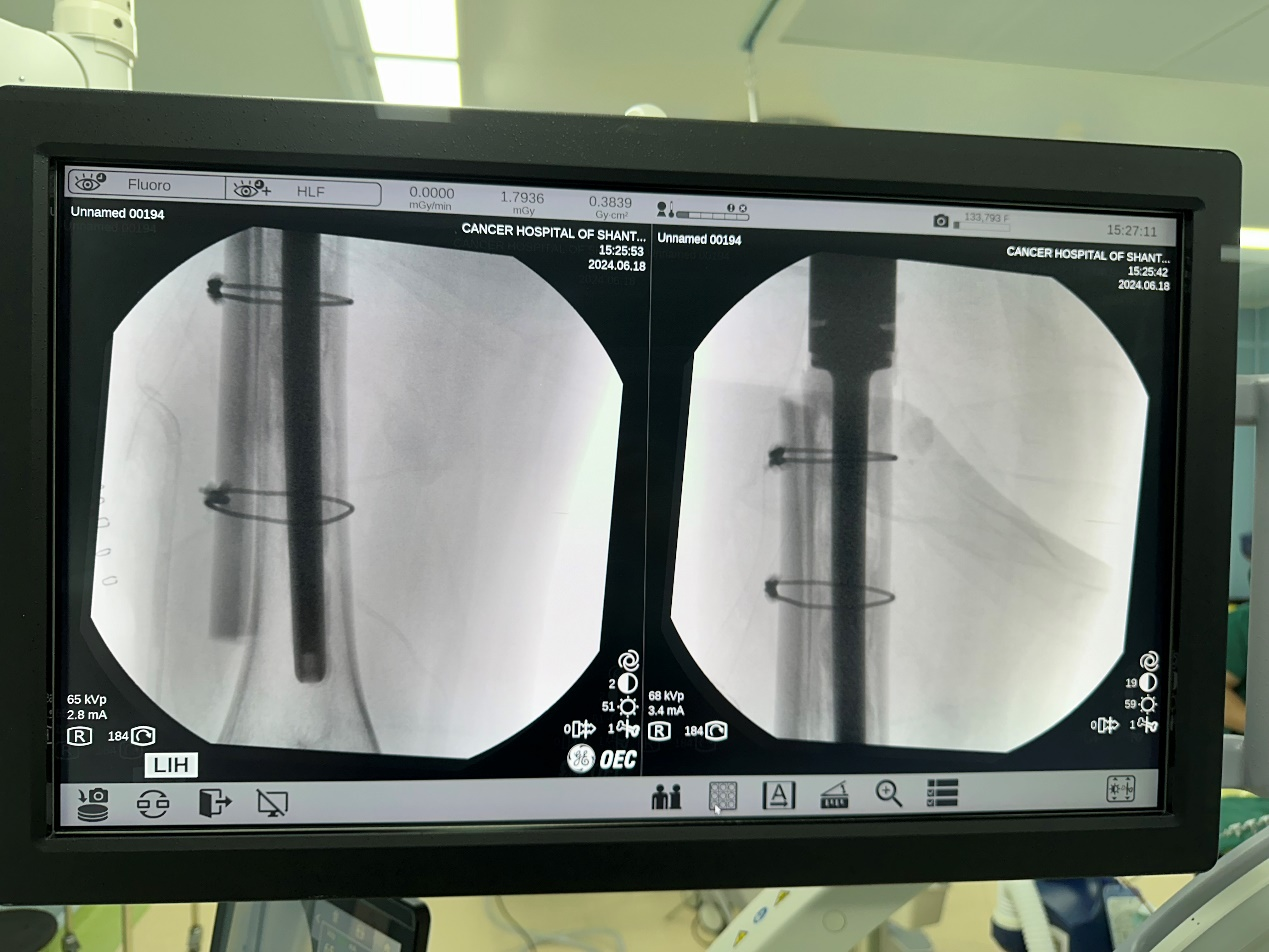

然而命运多舛,半年前他因为假体松动在外院进行了右人工股骨头翻修术,仅仅过了几个月,他再次感觉行走不稳,完善检查后发现再次出现假体松动并且假体柄断裂。转诊多家医院后,此次他决定到我院骨科门诊就诊。

图片 1.png图片 2.png

术前影像